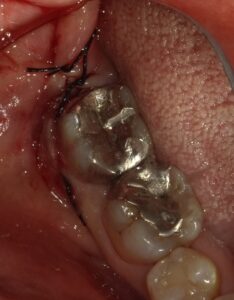

術前の状態です。仮のセメントが詰めてあります。

歯肉を切開し開いて青で囲った部分の虫歯を露出させます。

縫合を終えたところです。